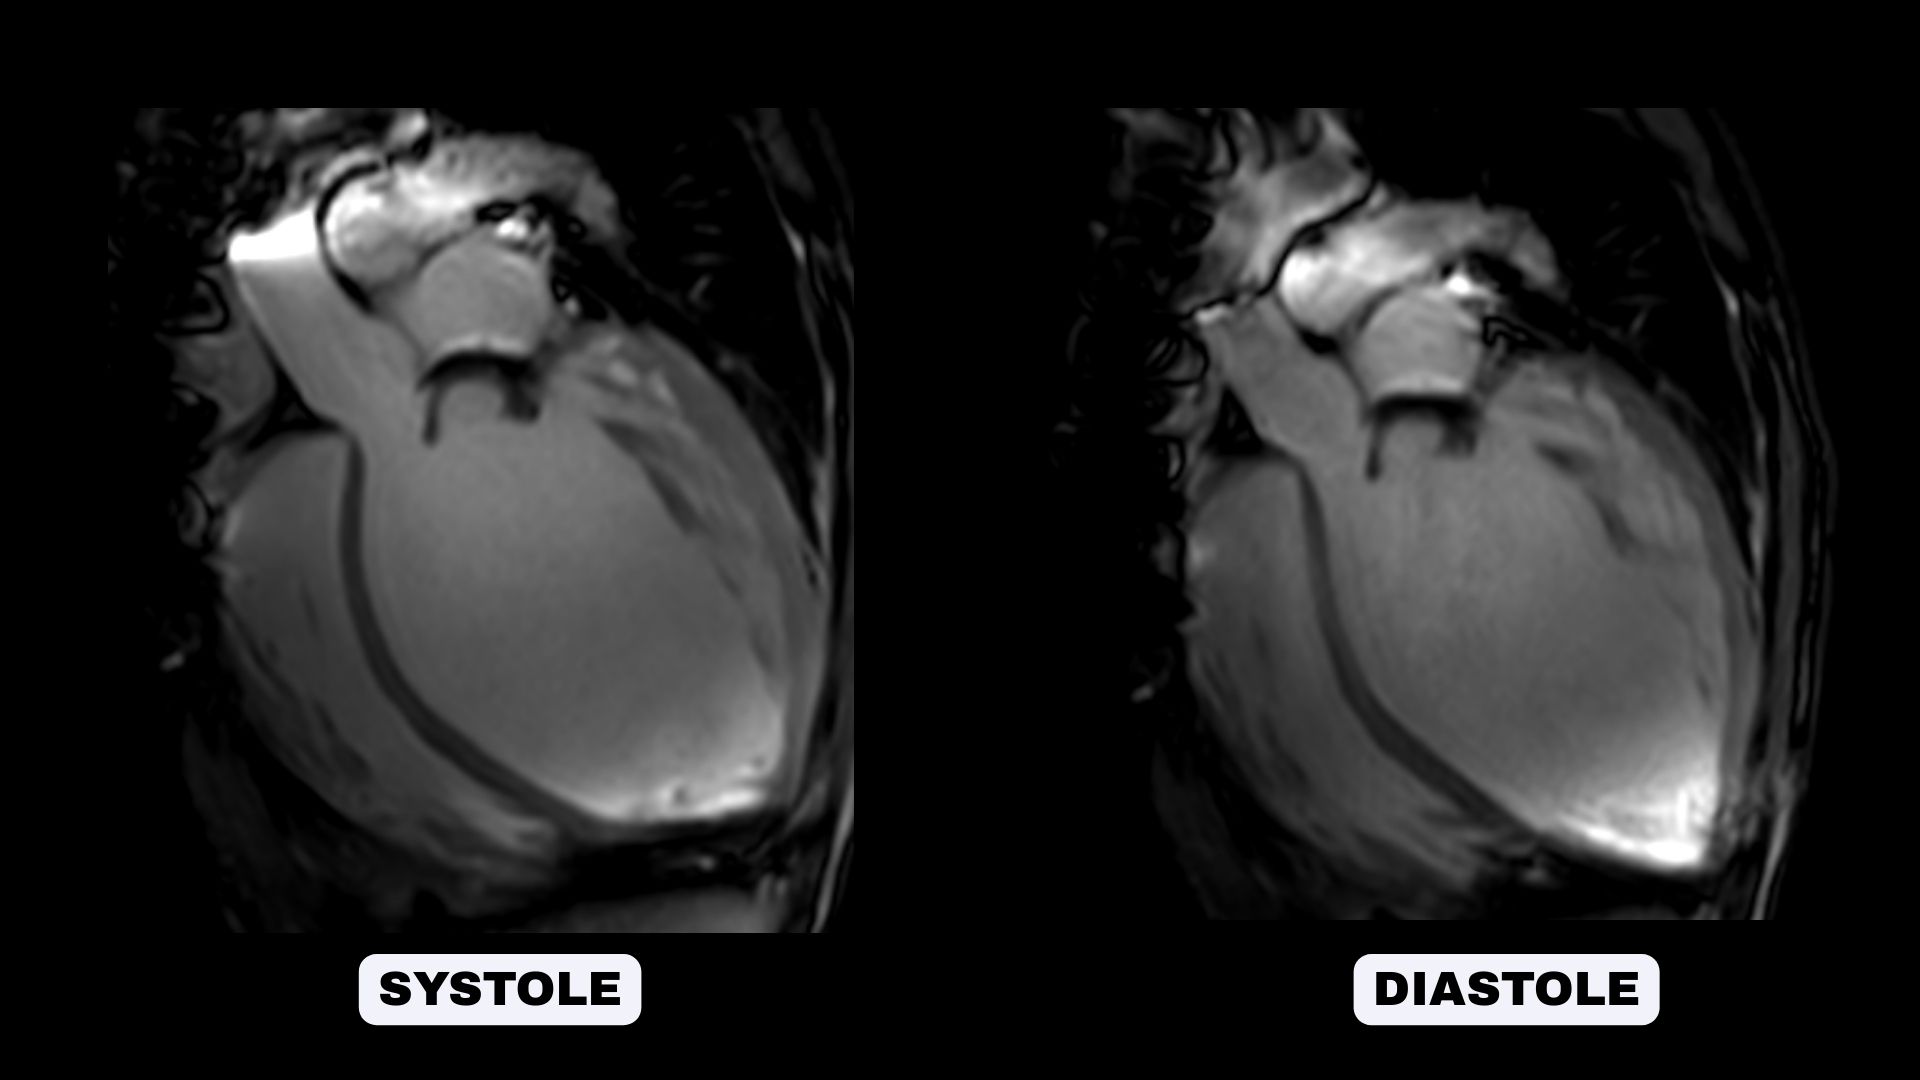

Cine SSFP sequences for morphological and functional evaluation